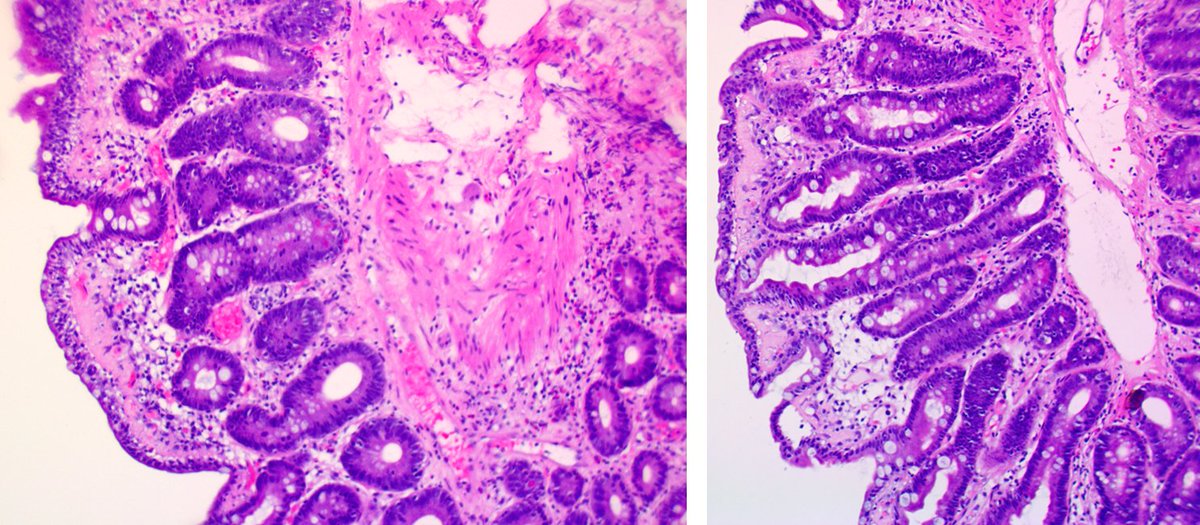

A teaching point from our Editors. How do you distinguish between intrapancreatic bile duct carcinoma and pancreatic ductal carcinoma? Samuel Freire